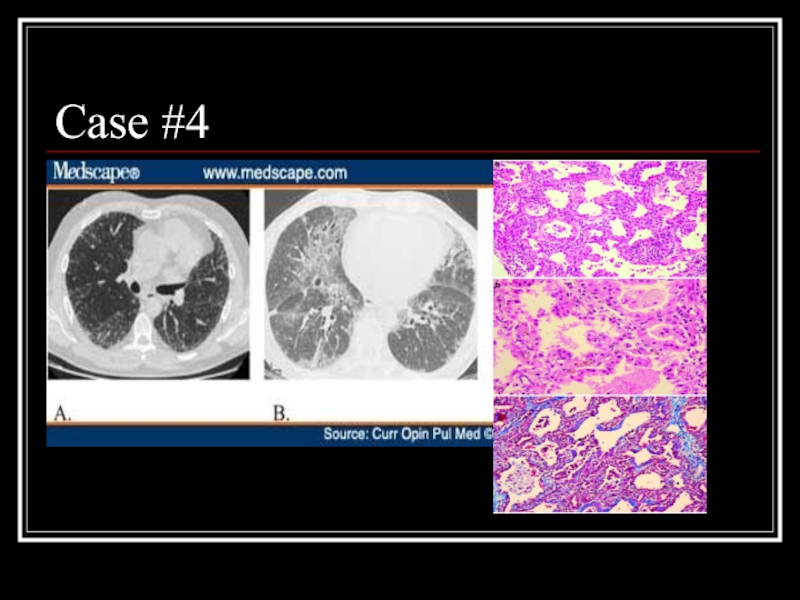

Слайд 25Case #4

Слайд 26Answer: NSIP

A: Fibrotic variant with reticular subpleural lines with uniform distribution,

bronchiolectasis, and areas of ground glass attenuation

B: Cellular variant with ground glass opacities and traction bronchiectasis

Path: homogeneous expansion of interstitium by inflammatory cells, myofibroblasts, and Type II pneumocytes hyperplasia